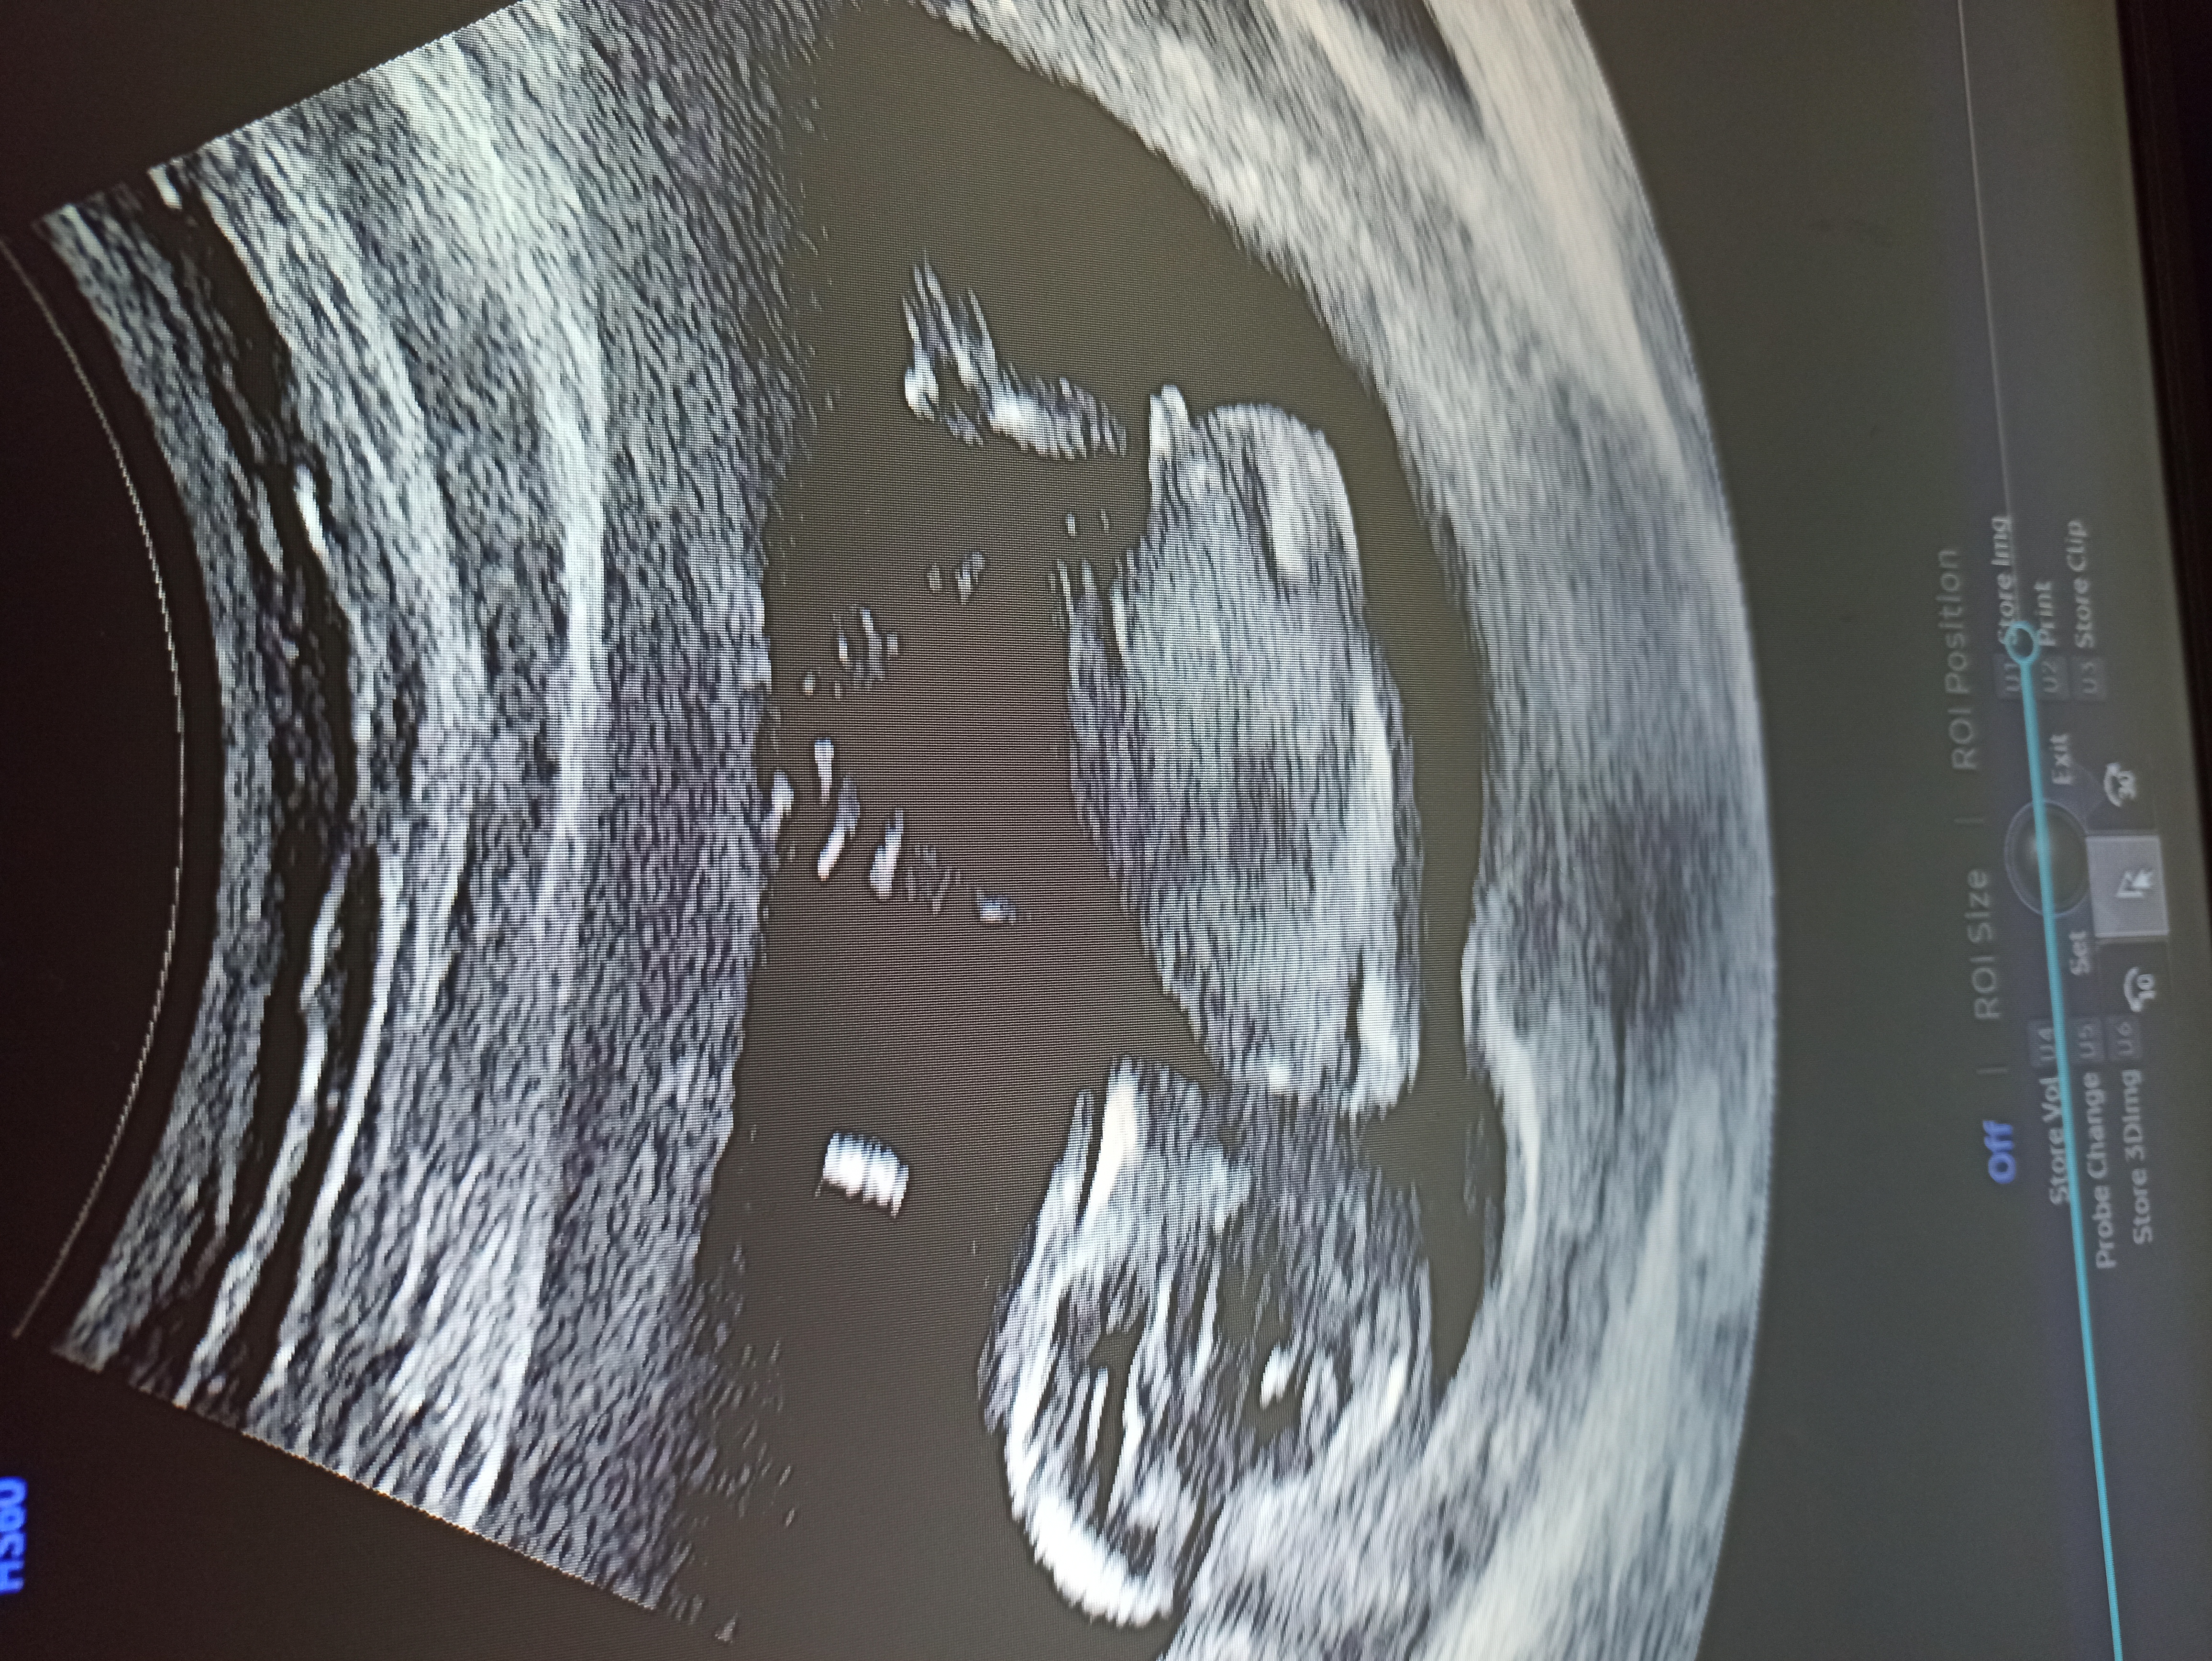

Dobrý den, myslíte, že lze na tomto snímku určit pohlaví miminka? Je to 12+6. Diky, foto v komentáři